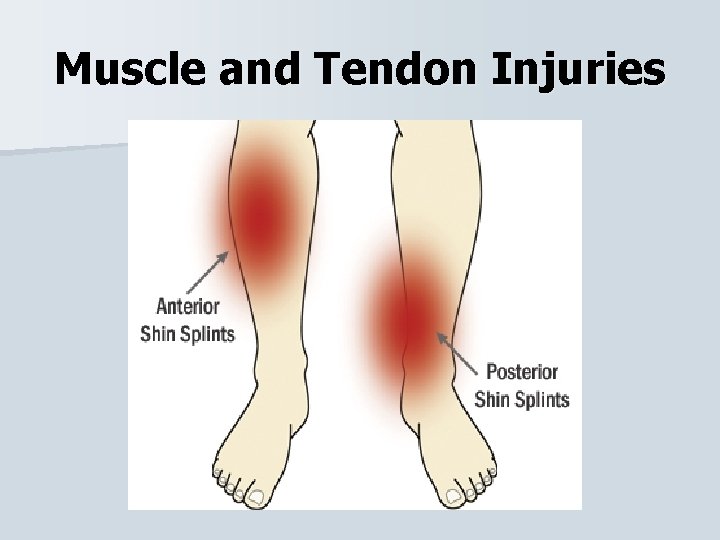

Muscle and Tendon Injuries Shin Splints “Medial tibial stress syndrome” A common term for lower leg pain that involves muscle fibers on medial side of the tibia to become irritated and torn. • Pain will be on the distal medial aspect of the shin. • This is generally caused from tight calves, older shoes, or out of shape. Pain can be relieved from PRICE. •